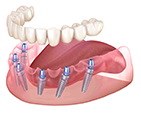

Восстановление зубов

All-on-4 (всё на 4-х)

All-on-4 (всё на 4-х)

Восстановление зубов

All-on-6 (всё на 6)

All-on-6 (всё на 6)

Бюджетная стоимость:

протез фиксируется

на 4-х имплантах

протез фиксируется

на 4-х имплантах

Зубы не отличаются

от натуральных

от натуральных

Жевательная функция

восстанавливается

полностью

восстанавливается

полностью

Можно восстановить

зубной ряд в самых

сложных случаях

зубной ряд в самых

сложных случаях